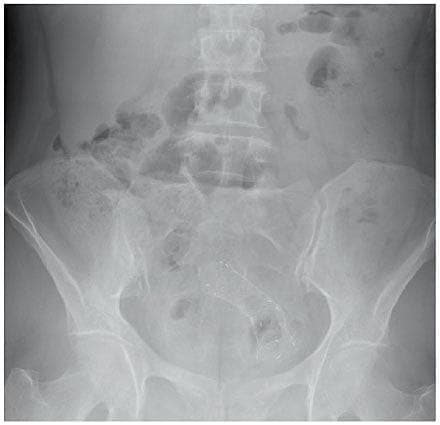

I 10-30% af tilfældene debuterer kolorektal cancer med akut obstruktion [1, 2]. Dette er en livstruende tilstand, der har dårlig prognose og kræver øjeblikkelig behandling, som traditionelt har været akut operation med resektion af det tumorbærende tarmstykke og anlæggelse af en stomi. Akut operation er dog associeret med en høj mortalitet (15-20%) og morbiditet (45-50%) [1, 2]. Behandling med selvekspanderende metalstent (SEMS) blev derfor introduceret som et alternativ hertil i begyndelsen af 1990’erne og har siden fundet stigende anvendelse [3, 4]. Indikationerne for brug af SEMS har dels været pallierende behandling af inoperabel cancer, og dels som bridge to surgery med henblik på senere elektiv radikal operation. Umiddelbart synes proceduren at være sikker og effektiv til akut behandling af malignt betinget kolorektal obstruktion [4]. Dette synspunkt er dog efterhånden blevet draget i tvivl af nogle [5], ligesom de onkologiske langtidsresultater synes at være uafklarede [6]. Formålet med denne artikel var derfor ved en litteraturgennemgang at søge at klarlægge den nuværende evidens for behandling af cancerbetinget kolorektal obstruktion med SEMS.

I den største prospektive, ukontrollerede multicenterundersøgelse af SEMS som bridge to surgery fra 2011 med i alt 182 patienter, hvor de samme 39 centre som i [7] deltog, fandt man en teknisk succesrate på 98%, en klinisk succesrate på 94% og en komplikationsrate på 8%, inklusive en perforationsrate på 3% [14]. Den procedurerelaterede mortalitet var 0,6%. Modsat ved akut operation kunne stomi undgås hos størstedelen af patienterne, idet kun ni af de 150 patienter (6%), der efterfølgende blev elektivt opereret, fik stomi. Det skal dog tilføjes, at komplikationsraten ved de senere elektive operationer var 16,6%, og mortaliteten 2%, hvilket naturligvis skal tages med

i den samlede vurdering af metoden.